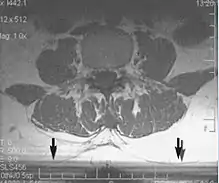

Fig. 3. Metal-related artifacts.[1]

Fig. 4. Metal-related artifacts.[1]

Metal artifacts occur at interfaces of tissues with different magnetic susceptibilities, which cause local magnetic fields to distort the external magnetic field. This distortion changes the precession frequency in the tissue leading to spatial mismapping of information. The degree of distortion depends on the type of metal (stainless steel having a greater distorting effect than titanium alloy), the type of interface (most striking effect at soft tissue-metal interfaces), pulse sequence and imaging parameters. Metal artifacts are caused by external ferromagnetics such as cobalt containing make-up, internal ferromagnetics such as surgical clips, spinal hardware and other orthopaedic devices, and in some cases, metallic objects swallowed by people with pica.[3] Manifestation of these artifacts is variable, including total signal loss, peripheral high signal and image distortion (Figs 3 and 4).[1] Reduction of these artifacts can be attempted by orientating the long axis of an implant or device parallel to the long axis of the external magnetic field, possible with mobile extremity imaging and an open magnet. Further methods used are choosing the appropriate frequency encoding direction, since metal artifacts are most pronounced in this direction, using smaller voxel sizes, fast imaging sequences, increased readout bandwidth and avoiding gradient-echo imaging when metal is present. A technique called MARS (metal artifact reduction sequence) applies an additional gradient, along the slice select gradient at the time the frequency encoding gradient is applied. ==Signal processing dependent artifacts== The ways in which the data are sampled, processed and mapped out on the image matrix manifest these artifacts.[1]